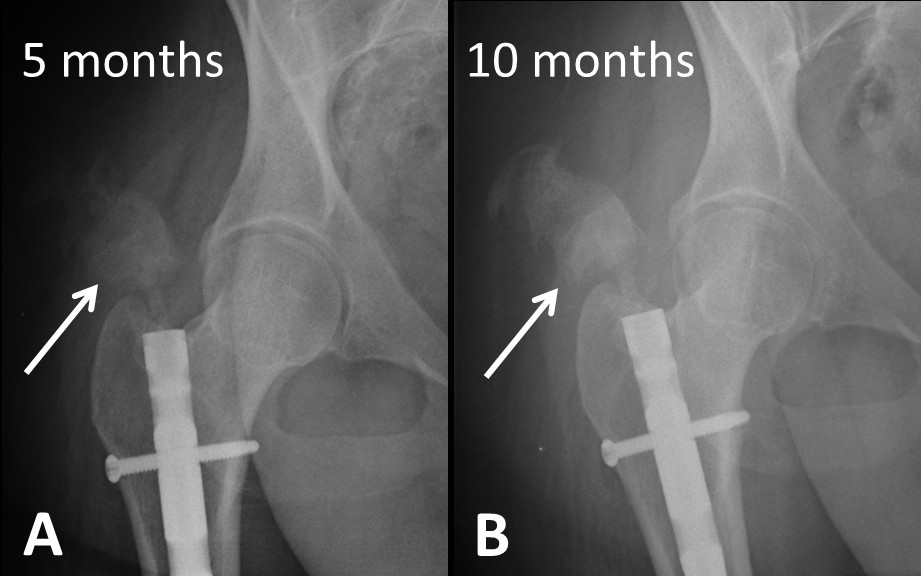

From jmedicalcasereports.biomedcentral.com

Heterotopic ossification in the reaming tract of a percutaneous What Is Femoral Reaming In general, reamed nailing allows the use of larger diameter implants and may therefore provide greater. Table 1 shows the frequency distribution of age and sex of. If the medullary canal is narrow, it may be necessary to enlarge it by reaming to allow the insertion of a larger diameter nail with sufficient strength. Reaming results in elevated temperature and. What Is Femoral Reaming.